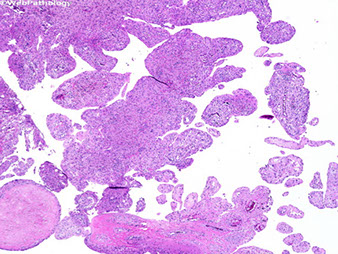

Anaplastic, high-grade malignant small round blue cell tumor MC in boys <15 yo

- may present as warmth and swelling in the diaphysis of long bones and in pelvis, scapula and ribs (bone involvement assoc c soft-tissue extension, can occur in any bone)

Micro: uniform small round blue cells, eosinophilic cytoplasm

- monotonous nuclei ,inconspicious nuclei and low mits are deceptively low grade

- occasionally has Rosettes

Ewing's sarcoma / PNET

A, Ewing sarcoma consists of solid sheets of small, blue, round cells with geographic necrosis and nuclear expression of Friend leukemia integration 1 transcription factor (FLI1) (B).